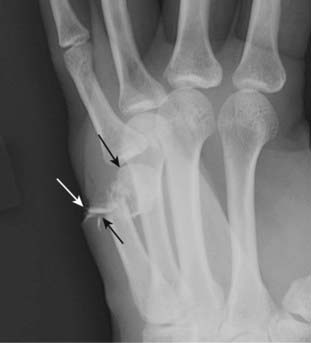

Figure 22-10 Open (compound) fracture, 5th metacarpal.

Most fractures are closed, meaning there is no communication between the fracture fragments and the outside atmosphere. Open or compound fractures (solid black arrows) have communication between the fracture and the outside (solid white arrow). Whether a fracture is open or not is best evaluated clinically. Treatment of a compound fracture must consider the higher incidence of infection that can occur in these injuries.